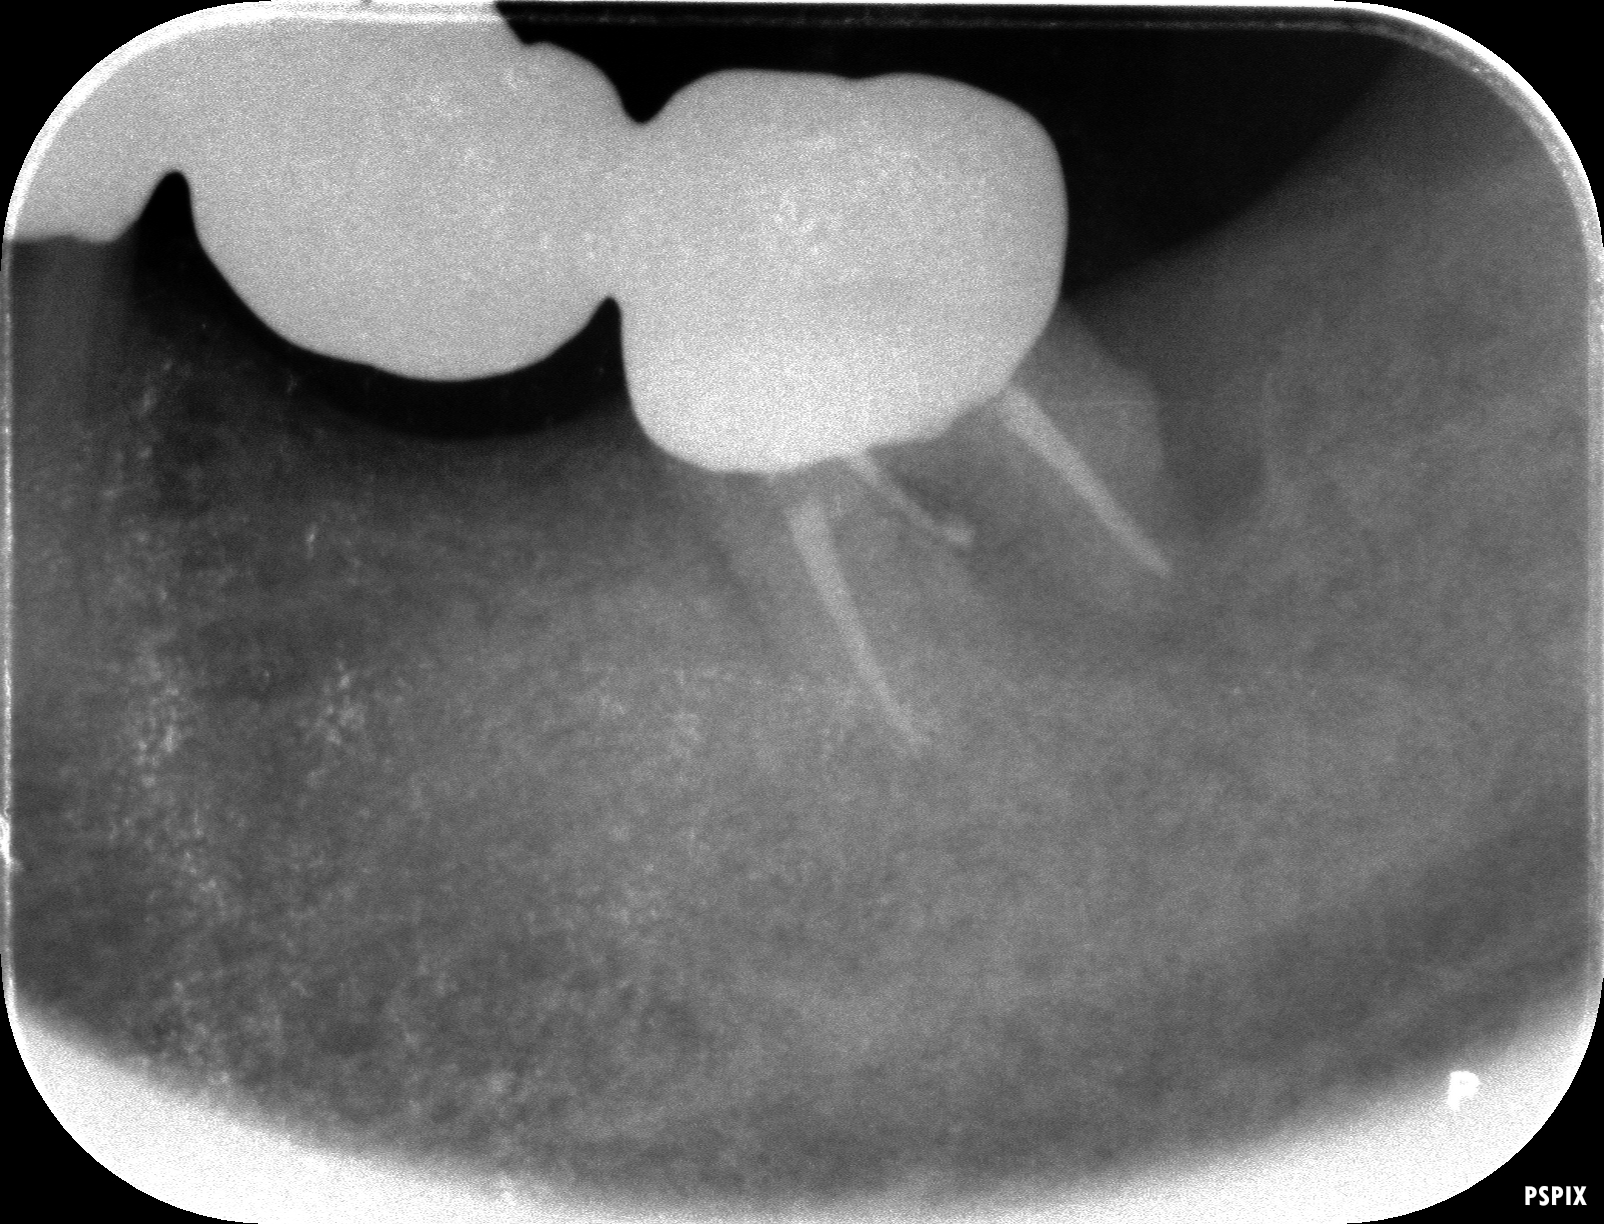

再植術後のレントゲンがこちらです。歯の周りの骨が大分黒くなっています。この状態が骨が無い状態です。

被せ物を入れ半年経過時です。根の周りの黒い像も大分回復してきています。